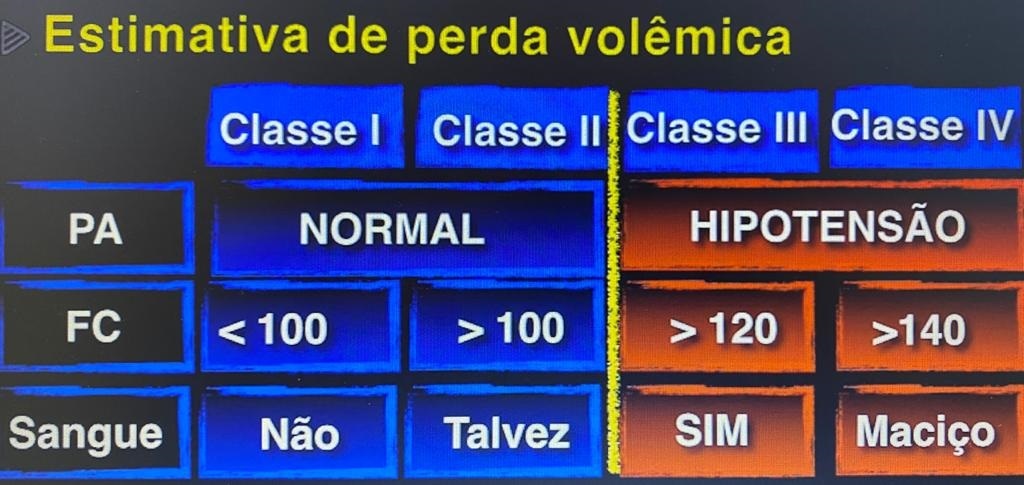

- Estimativa da perda volêmica

Indicado: refratariedade a reposição inicial com 1 L de volume, classe 4